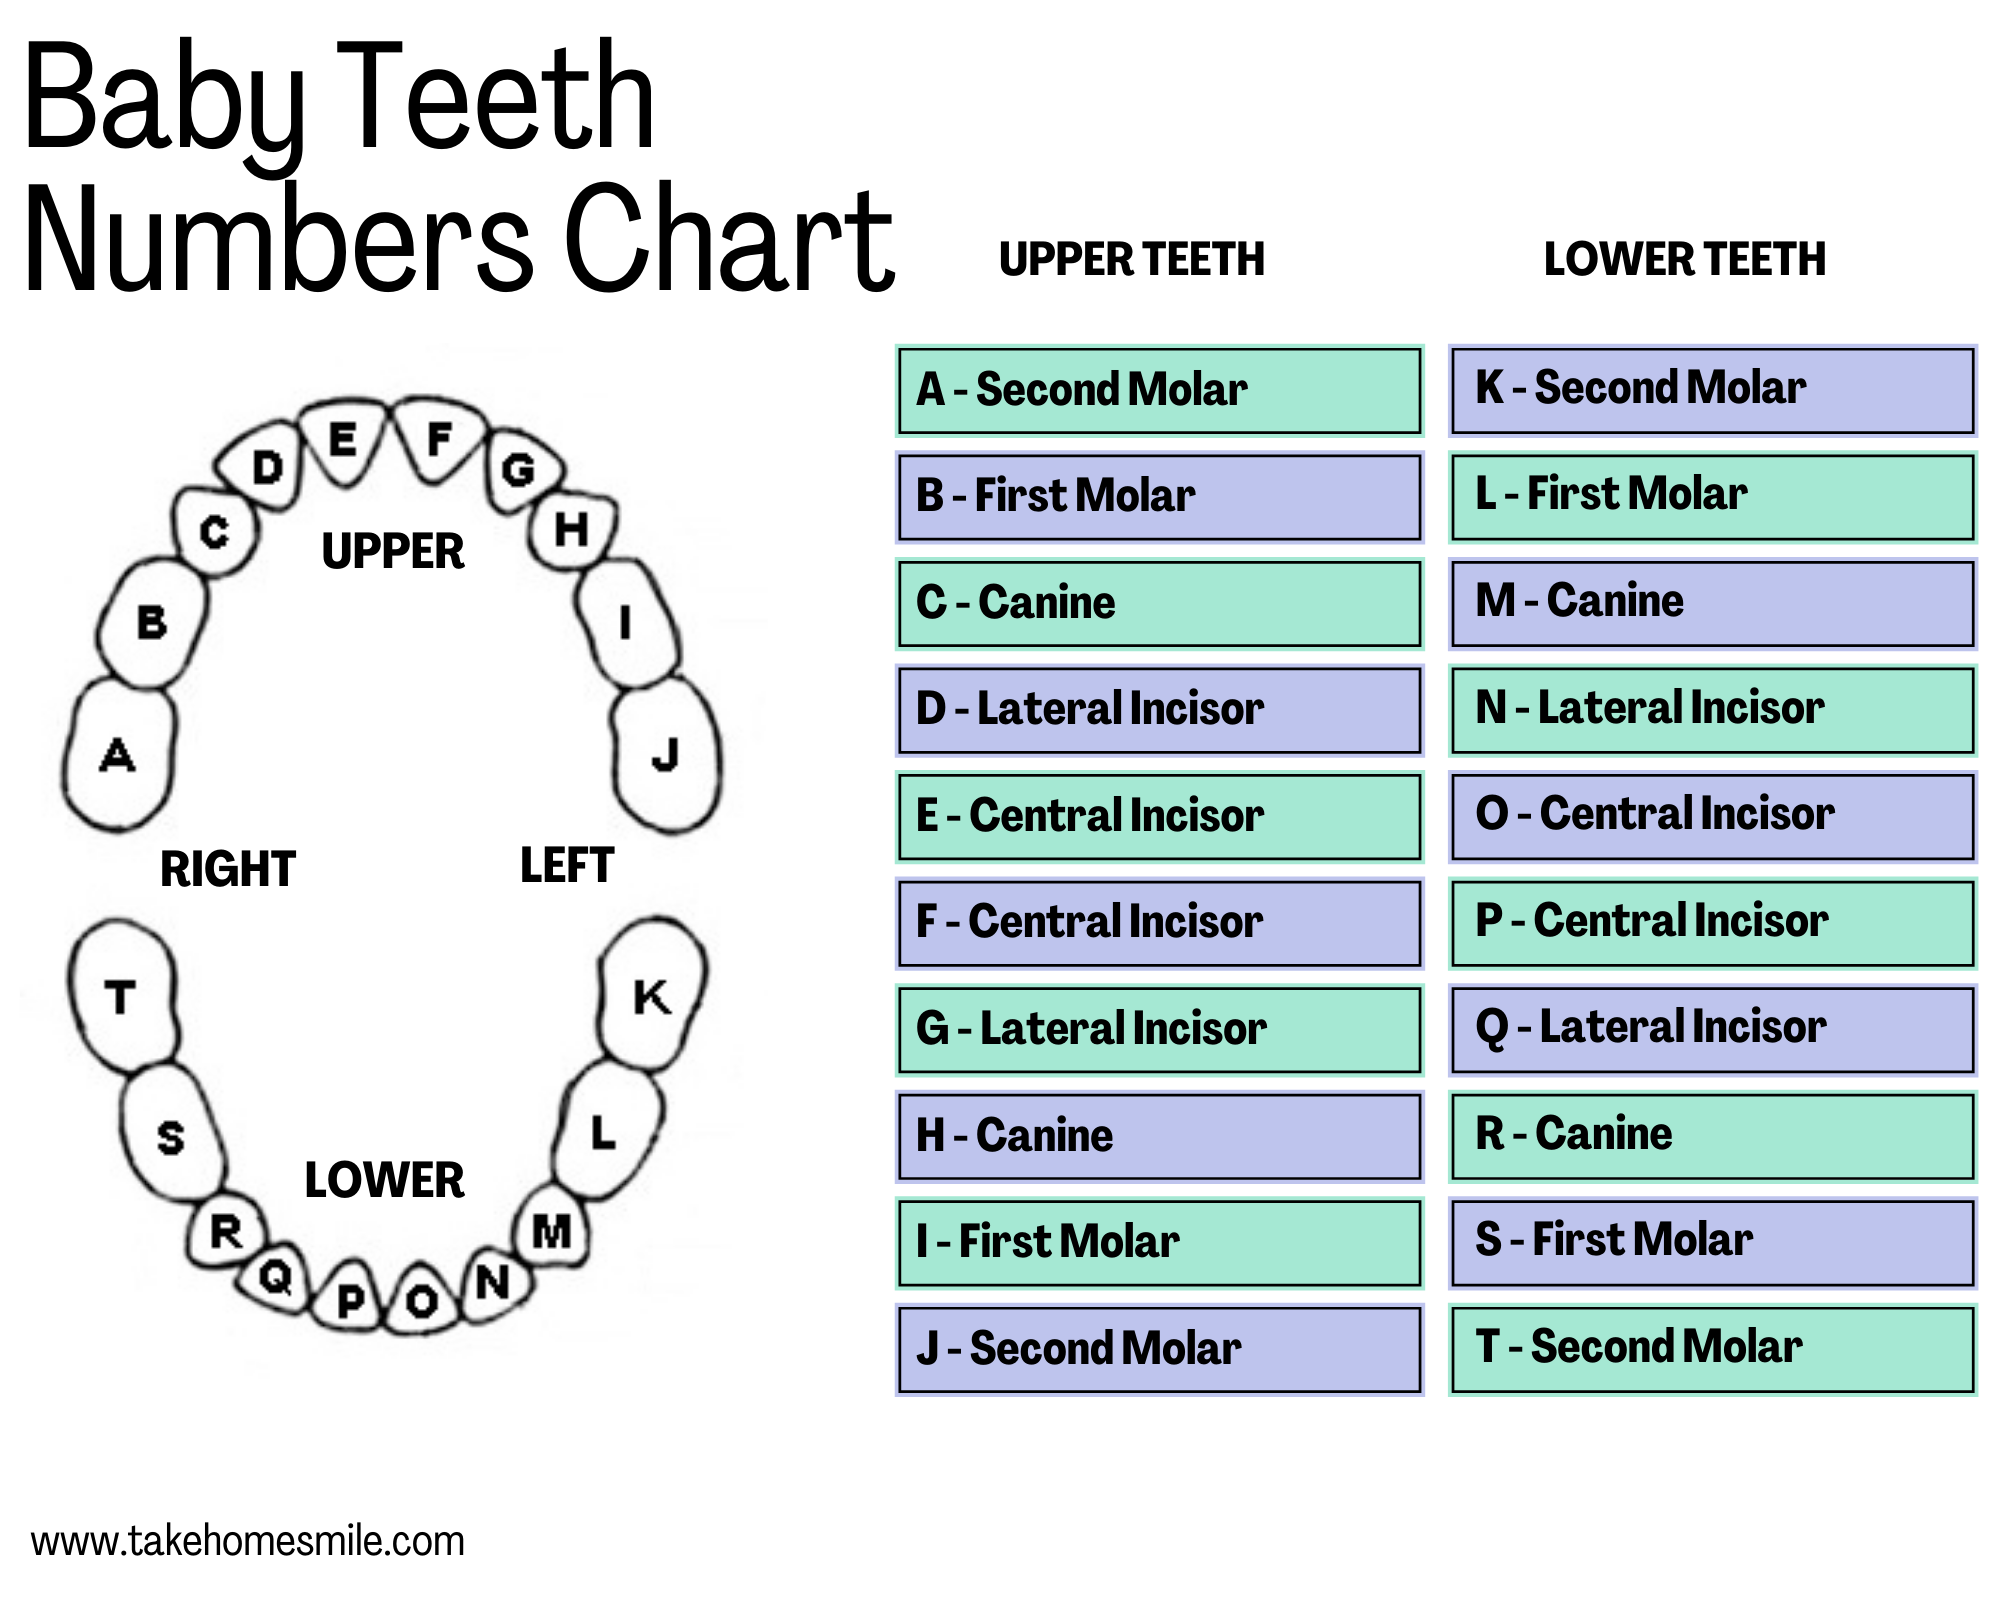

Understanding Teeth Numbers: A Visual Guide - Take Home Smile

takehomesmile.com999 Mẫu Dental Desktop Backgrounds Chất Lượng HD, Tải Ngay

takehomesmile.com999 Mẫu Dental Desktop Backgrounds Chất Lượng HD, Tải Ngay

wallpapers.comPrimary Teeth Chart Letters

wallpapers.comPrimary Teeth Chart Letters